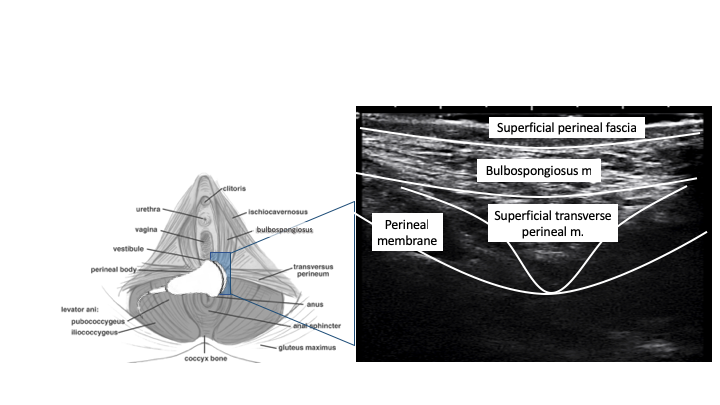

B Mode ultrasound of left perineal body

B Mode ultrasound of right perineal body